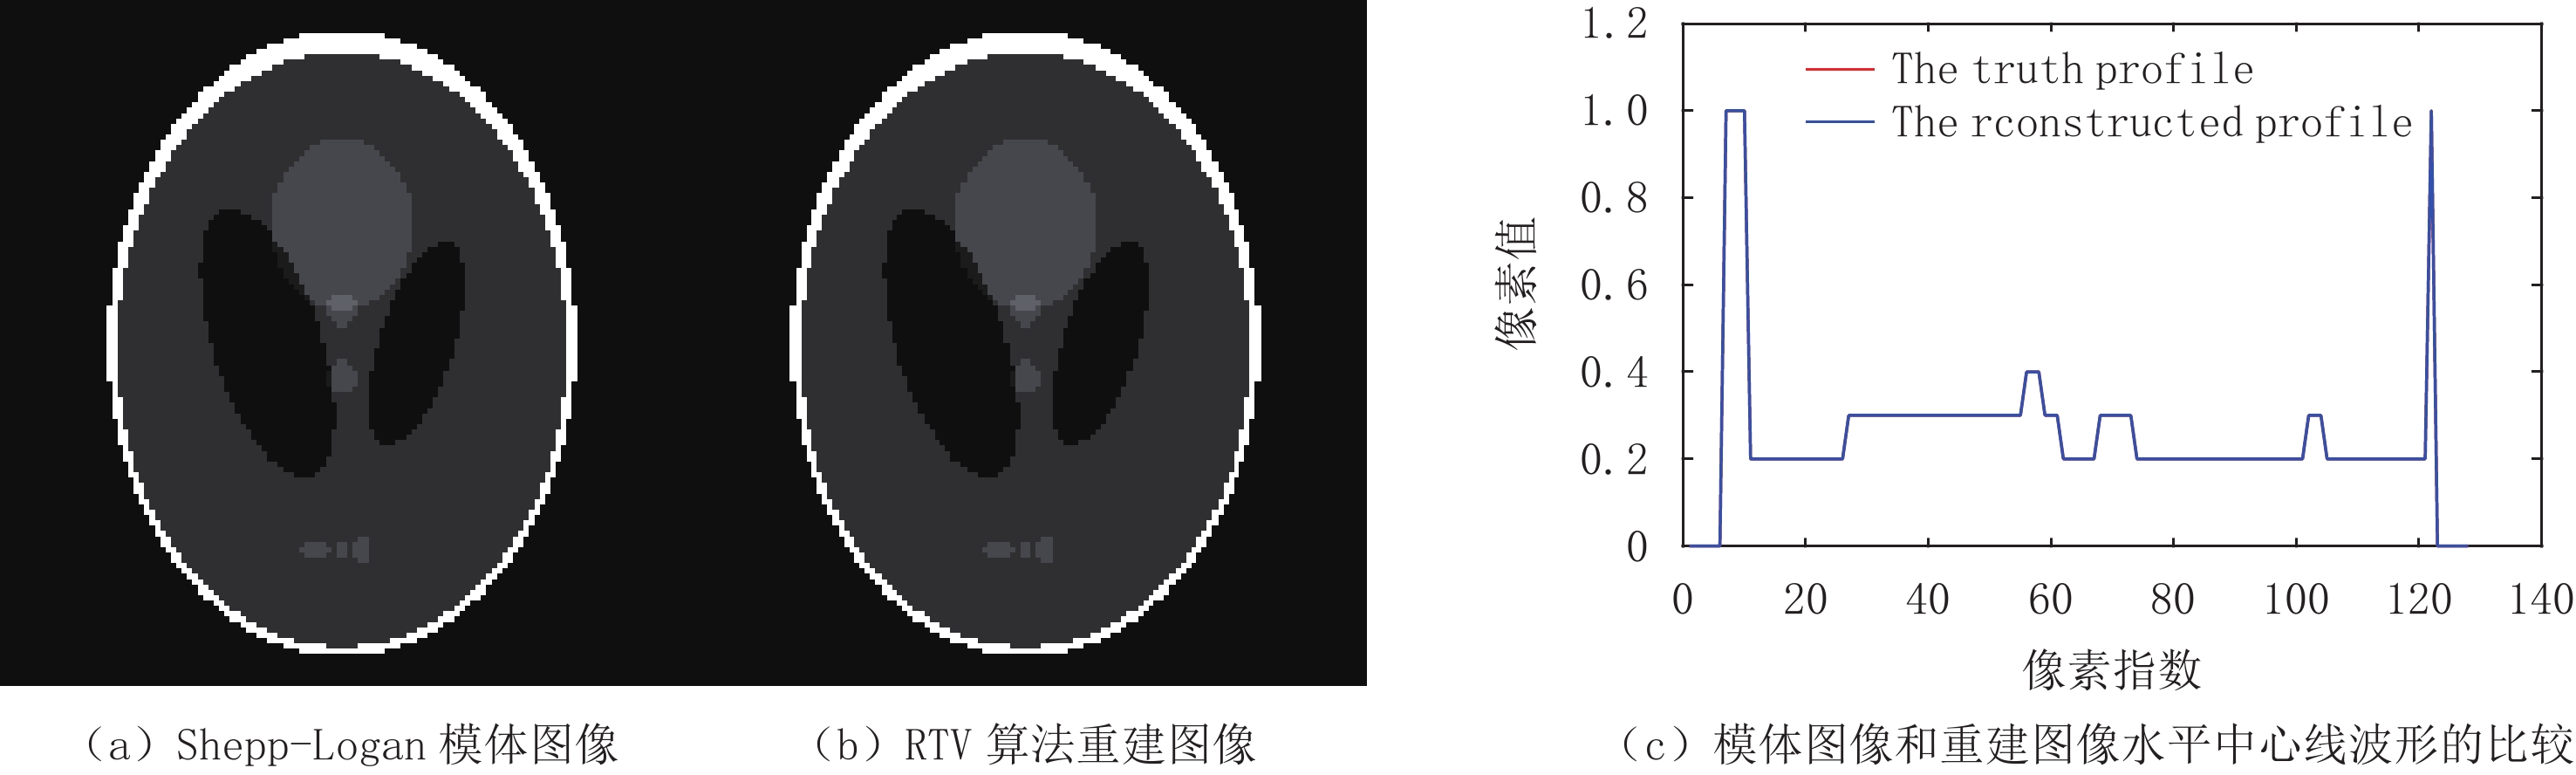

${{\boldsymbol{f}}_{{\rm{res}}}}$ 是重建图像的向量表示,${{\boldsymbol{f}}_{{\rm{truth}}}}$ 是真实图像的向量表示,N为向量长度。$$ {{\rm{RMSE}}\left( {{{\boldsymbol{f}}_{{\rm{rec}}}},{{\boldsymbol{f}}_{{\rm{truth}}}}} \right) = \frac{{{{\big\| {{{\boldsymbol{f}}_{{\rm{rec}}}} - {{\boldsymbol{f}}_{{\rm{truth}}}}} \big\|}_2}}}{{\sqrt N }}} 。 $$ (17) 对于Shepp-Logan模体和FORBILD模体重建来说,当RTV最小化算法分别迭代到200次和300次左右时,其各自的RMSE已经小于10-4,符合该实验定量分析正确性的标准。而从重建结果来看,如图2和图3所示,其中(a)图是Shepp-Logan和FORBILD仿真模型图像;(b)是实现收敛的重建图像;(c)是(a)、(b)两幅图像中心线波形的比较。从图2和图3可见(a)、(b)两幅图几乎完全一样,难以分辨彼此。从(c)图可见(a)、(b)两幅图的中心线波形几乎完全重合。对重建图像和中心线波形的观察表明,该算法实现了高精度重建,符合该实验定性观察正确性的标准。

总的来说,无论是从重建结果的定性观察,还是重建图像的RMSE小于

${10^{ - 4}}$ 来看,都可以说明该实验的正确性研究是成功的,从而说明所构建的模型及代码实现是正确的。3.1.3 RTV最小化重建算法的收敛性评估